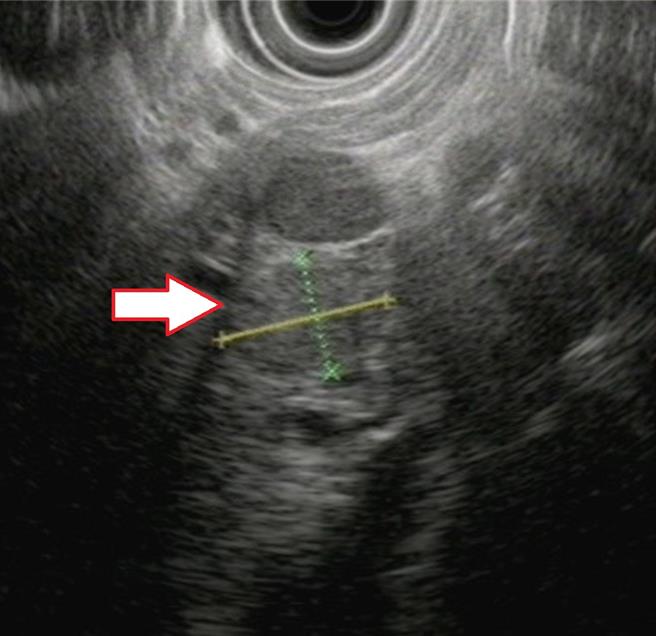

亚洲大学附属医院新陈代谢科医师王子源表示,透过内视镜超音波检查可察觉胰臟异状。(亚大医院提供/冯惠宜台中传真)

王子源说,直到半年后患者到诊所健康检查抽血,发现严重低血糖,经转介来门诊寻找病因,由于过去曾诊疗过类似病例,综合前述异常举止及自发性低血糖等症状,怀疑恐是罕见的「胰岛素瘤」,于是安排病患住院检查,也透过腹部电脑断层及内视镜超音波检查,发现胰臟的头部有一颗约1.4公分的肿瘤。